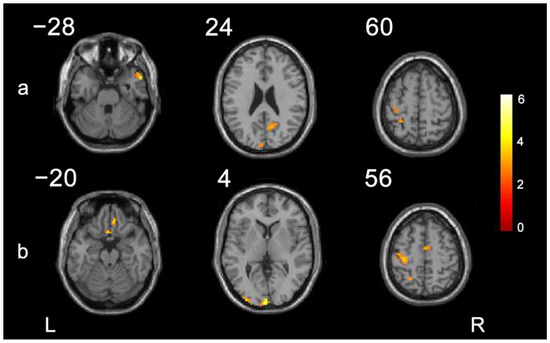

| ROI | Cluster | Connected Region | Peak MNI Coordinates | Peak F Value | Cluster Size | ||

|---|---|---|---|---|---|---|---|

| X | Y | Z | |||||

| M1 (ipsilesional side) | 1 | Precentral_L * | −39 | −21 | 63 | 2.78 | 17 |

| 2 | Postcentral_L * | −27 | −42 | 60 | 3.17 | 12 | |

| 3 | Postcentral_L * | −15 | −39 | 78 | 3.88 | 11 | |

| 4 | Calcarine_L | 0 | −99 | 3 | 5.52 | 57 | |

| 5 | Temporal_Pole_Mid_R | 57 | 12 | −27 | 3.94 | 13 | |

| 6 | Precuneus_R | 12 | −63 | 24 | 3.34 | 34 | |

| PMC (ipsilesional side) | 1 | Precentral_L * | −33 | −24 | 60 | 3.96 | 70 |

| 2 | Rectus_L,Olfactory_L | 0 | 18 | −21 | 3.62 | 11 | |

| 3 | Occipital_Mid_L | −36 | −96 | 0 | 4.15 | 23 | |

| 4 | Parietal_Sup_L | −24 | −54 | 54 | 3.27 | 12 | |

| 5 | Calcarine_L | 0 | −99 | 3 | 5.48 | 43 | |

| 6 | Supp_Motor_Area_R | 3 | −6 | 60 | 3.55 | 16 | |

| 7 | Rectus_R | 9 | 36 | −21 | 3.55 | 14 | |